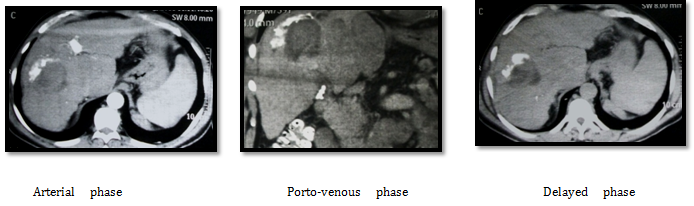

CT images after three weeks from RF ablation: Post RF CT showing partial about 50% ablation of the lesion with residual tumoral reactivity and newly developed intra-lesional portal shunts. Then we decided to complete treatment by TACE after one month from RF ablation. 1st we did angiography that revealed right hepatic artery superior branch small aneurysmal dilatation (pseudo-aneurysm), that is appears after RF ablation. It was affecting the flow as seen in next images (Figure 8). So we decided to embolize the aneurysm and correct the flow into the tumoral tissue as seen in the following images (Figure 9). Lastly we injected the chemo-lipiodol mixture into the right lobe lesion (Figure 10).

Figure 8 CT Images after three weeks from RF ablation.

Figure 9 Flow into the tumoral tissue.

Figure 10 Chemo-lipiodol mixture into the right lobe lesion.

Follow up by triphasic CT after 3 months of combined therapy showing: Good uptake of lipiodol droplet by all residual tumoral tissues with small segment VIII residual active lesion that were noticed and treated by another session of TACE after one month (Figure 11). After 8 month patient developed two new left hepatic focal lesions and small satellites around the 1st ablated one with mild elevation of AFP reaching 50IU/DL that is further retreated by TACE. After 12month patient follow up showing no newly developed lesions with AFP reaching 25 IU/DL (Figure 12).